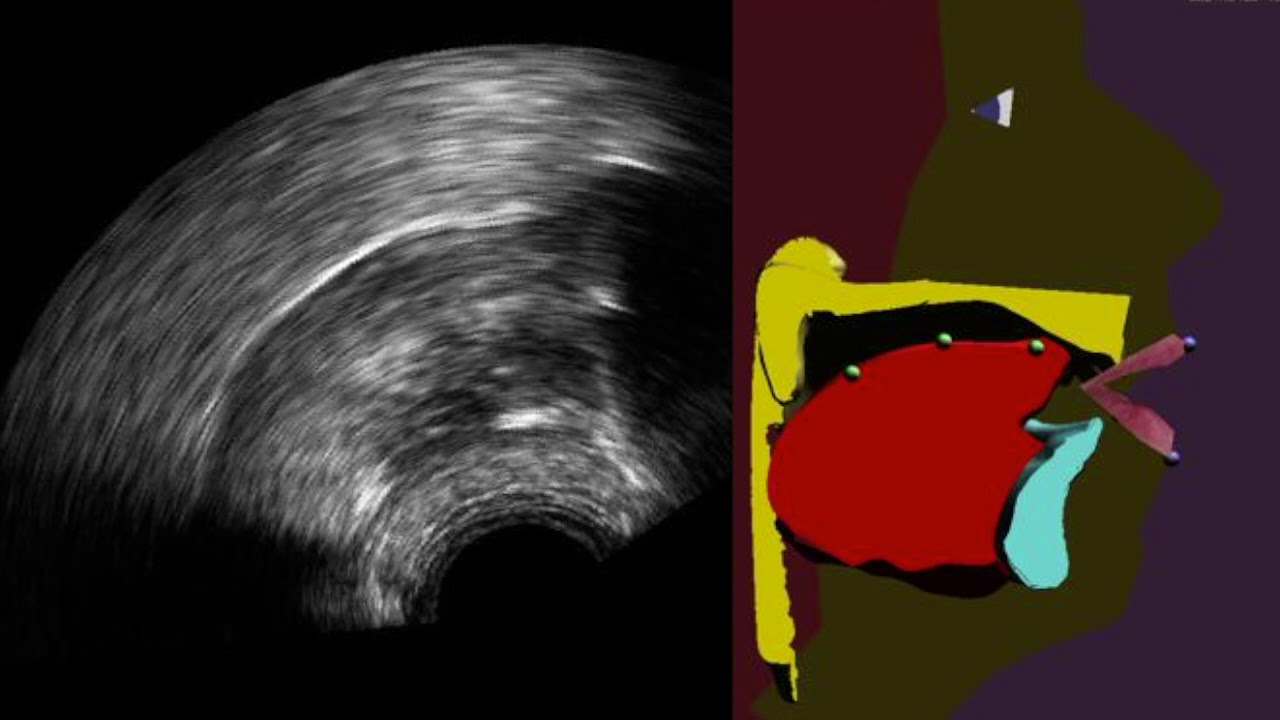

Imagen del nuevo sistema. A la izquierda, ecografía del sistema lingual, a la derecha, la reconstrucción virtual que permite observar en tiempo real los movimientos de la lengua y descubrir los defectos en la pronunciación. Imagen: CNRS

Investigadores franceses han desarrollado un sistema que permite visualizar, en tiempo real, los movimientos de nuestra lengua. Se trata de una ecografía lingual aumentada que, además de mostrar el rostro y los labios, hace aparecer la lengua, el paladar y los dientes, generalmente ocultos en el interior de la boca.

Los movimientos de la lengua son capturados con la ayuda de una sonda ecográfica situada debajo de la mandíbula, y a continuación procesados por un algoritmo de aprendizaje automático que permite pilotar una especia de “cabeza parlante articulatoria”.

En el nuevo trabajo, los investigadores franceses mejoran este retorno visual a través de una especie de cabeza parlante articulatoria que es animada automáticamente en tiempo real a partir de imágenes ecográficas apoyadas con un algoritmo, según se explica en un comunicado.

Este clon virtual de una persona parlante permite una visualización del proceso físico de articulación de una lengua y su pronunciación mucho más intuitiva y contextualizada.

En el nuevo trabajo, los investigadores franceses mejoran este retorno visual a través de una especie de cabeza parlante articulatoria que es animada automáticamente en tiempo real a partir de imágenes ecográficas apoyadas con un algoritmo, según se explica en un comunicado.

Este clon virtual de una persona parlante permite una visualización del proceso físico de articulación de una lengua y su pronunciación mucho más intuitiva y contextualizada.